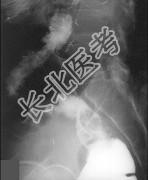

- 单项选择题女,50岁, 便血10余年,加重1年(连续出血), 近2个月大便时肛门常滴鲜血,量较多, X线检查如图,最可能的诊断为 ( )

E、直肠绒毛状腺瘤